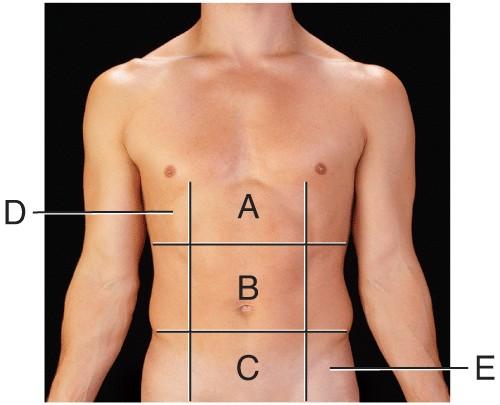

Name the region B.

middle hypochondriac

hypogastric

epigastric

Umbilical

Umbilical

Name the region A.

epigastric

umbilical

right hypochondriac

hypogastric

epigastric

Name the region E.

left hypochondriac

right lumbar

epigastric

left iliac

left iliac

Name the region C.

middle iliac

epigastric

umbilical

hypogastric

hypogastric

Name the region D.

Right Hypochondriac

Left Hypochondriac

epigastric

Right Lumbar

Right Hypochondriac

The liver is found in the region labeled:

A